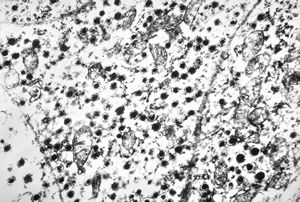

M,50y. | Pneumocystis carinii - lung